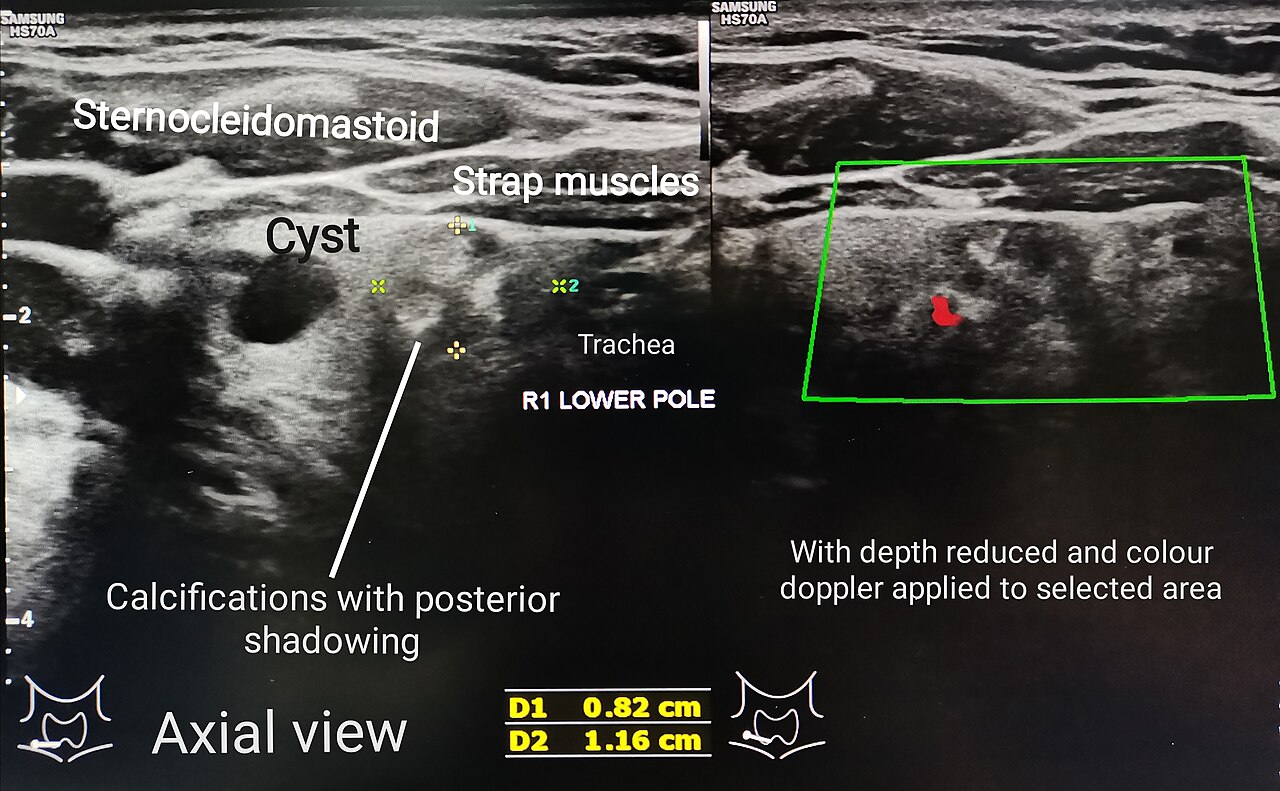

Thyroid phantom for ultrasound and nuclear medicine imaging